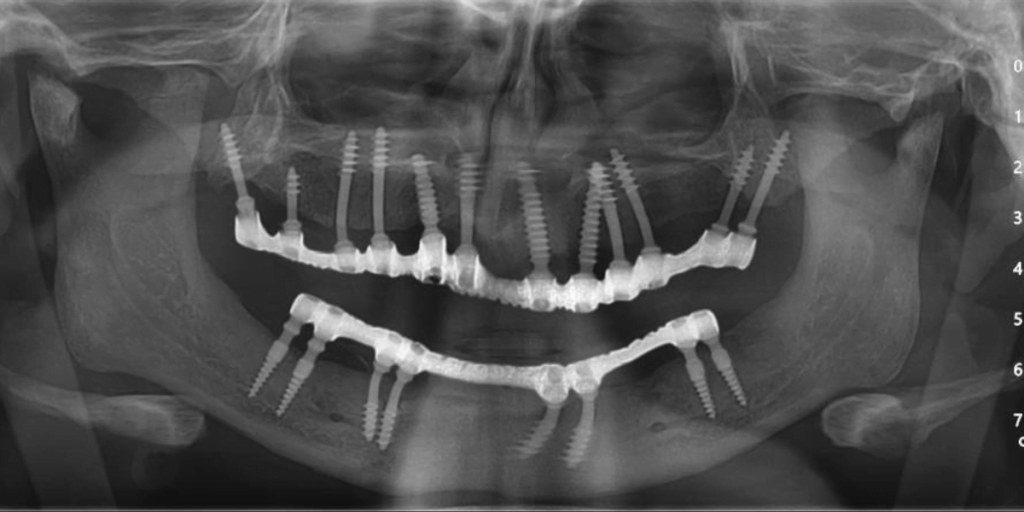

Rickets is a condition characterized by severe calcium insufficiency and low bone integrity, which poses substantial hurdles to dental rehabilitation. Patients with rickets frequently experience early tooth loss and skeletal malformations, which impair their ability to walk and stand normally. The Best Implantologist in Delhi NCR – Dr. Vivek Gaur, successfully handled one such patient. This case study looks at a ten-year follow-up on a patient with severe calcium shortage who had a complete mouth rehabilitation with Corticobasal® implantology while adhering to an immediate functional loading protocol.

➔Pre-Surgical Assessment: A thorough examination of bone quality and general health. It involved blood testing, X-rays, and 3D imaging to map the jaw anatomy.

➔Surgical Phase: Corticobasal® implants are placed after an immediate functional loading protocol. These implants are made to anchor in the basal bone, which is unaffected by rickets-related problems withv Regardless of the bone quality.

During the 10-year follow-up, the patient showed impressive improvement:

★Implant Success: All implants remained stable, showing no evidence of rejection or failure.